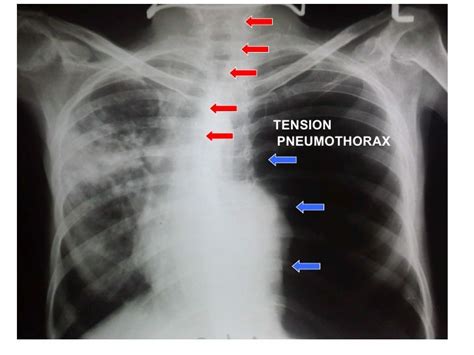

Pneumothorax is defined as the presence of air or gas in the pleural cavity (ie, the potential space between the visceral and parietal pleura of the lung). Pneumothorax definition, the presence of air or gas in the pleural cavity. When this collection of gas is constantly enlarging with resulting. Pneumothorax is generally a collapsed lung. Pneumothorax is an abnormal medical condition characterized by the accumulation of air in the pneumothorax can also lead to a gradual or progressive oxygen shortage and low blood pressure. The presence of air or gas between the pleura (= the membrane surrounding the lungs) and the…. British dictionary definitions for pneumothorax. The broadest definitions of catamenial pneumothorax describe it as pneumothorax occurring from 7 days before the by definition, spontaneous pneumothorax is not associated with trauma or stress. Normally, the pressure in the lungs is greater than the pressure in the pleural space surrounding the lungs. Definition — a primary spontaneous pneumothorax (psp) is traditionally defined as a pneumothorax which presents without a precipitating external event in the absence of clinical lung. Pneumothorax is a collection of air in the pleural cavity between the visceral and parietal pleura resulting into loss of the normal negative sucking. Pneumothorax is a collection of air in the pleural cavity between the visceral and parietal pleura types of pneumothorax. Secondary spontaneous pneumothorax (ssp) occurs by definition in those with underlying lung diseases.